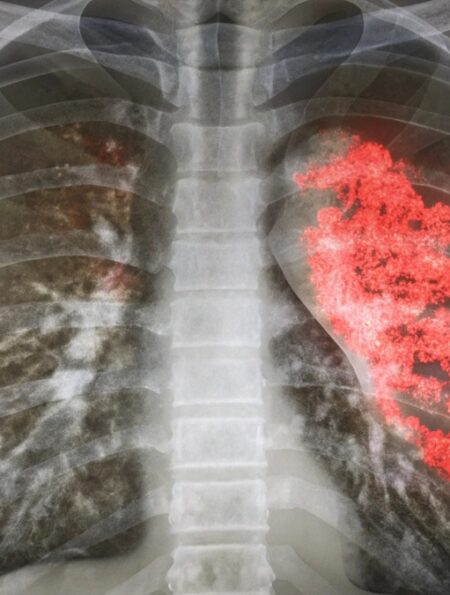

Astăzi, 24 februarie, când în tradiția românească se sărbătorește Dragobetele, vorbim despre „fluturii din stomac” și din perspectivă medicală. Iubirea.